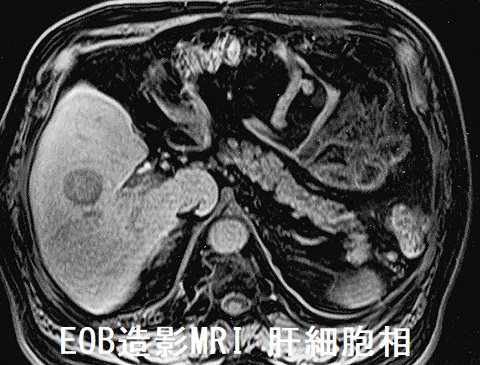

肝細胞癌で甲状腺機能低下症

肝血管腫と同じメカニズムか分かりませんが、肝細胞癌で著明な甲状腺機能低下症をおこす症例も報告されています。

福井県済生会病院の報告は、チラーヂンS 300μg,チロナミン50μg,チラーヂンS 坐薬200μg 投与してもTSH 175.3 μIU/mL の超重症甲状腺機能低下症でした。慢性C型肝炎の経過観察中に見つかった肝細胞癌に経皮的肝動脈塞栓術(TAE)を施行後、チラーヂンS 75μg のみでTSH 0.36 μIU/mLに改善したそうです。(第57回日本甲状腺学会 P1-050 肝細胞癌TAE 治療後に治療抵抗性甲状腺機能低下状態が著明に改善を認めた1 症例)

肝血管腫と同じく肝細胞癌においても、甲状腺ホルモンを不活化する3型脱ヨード酵素(DIO3)[T4→rT3, T3→T2]により甲状腺ホルモンが過剰に分解され、甲状腺機能低下症になる可能性が考えられます。